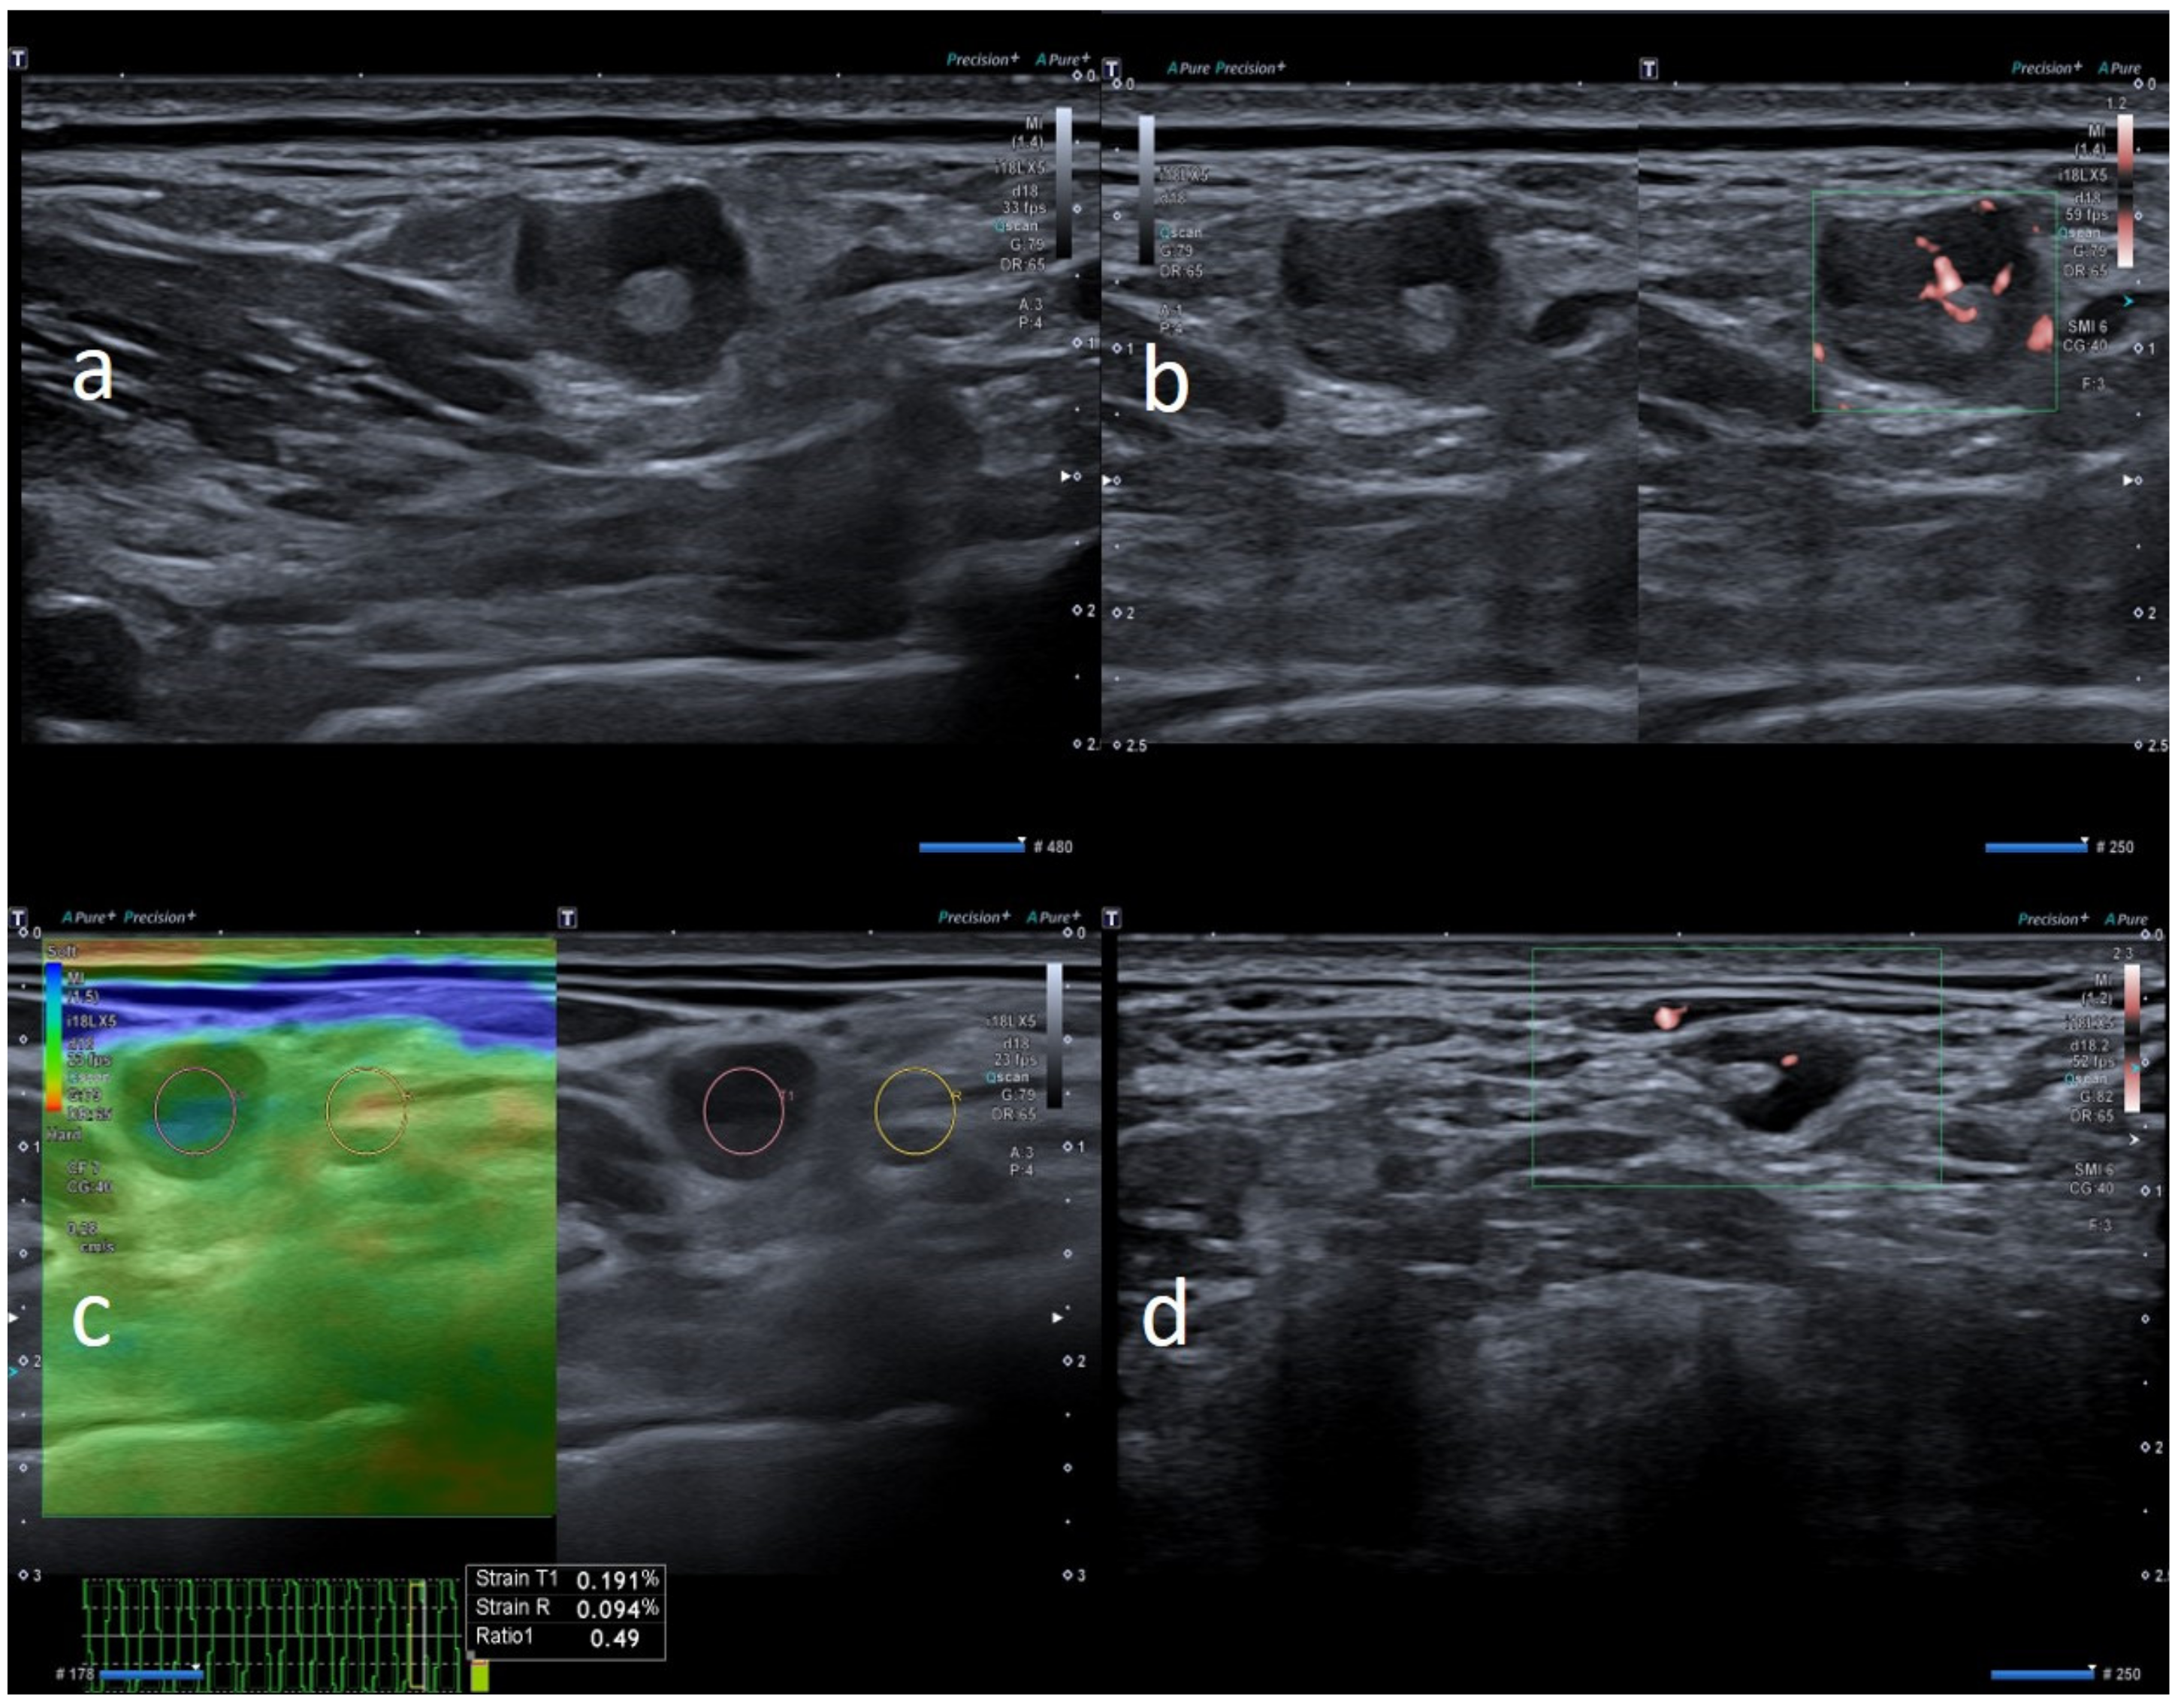

| M | 42 | Pfizer | Axillary ipsilateral to vaccine injection | Occasionally 1 weeks after second dose during chest ct | None | 3 | Variable: from 1.5 to 2.0 cm | Ovular | Simmetric cortical thickening with normal hilum | Stiffness similar to surrounding tissue | Normal | Unnecessary other follow-up |

| W | 49 | Pfizer | Axillary ipsilateral to vaccine injection | Occasionally, 6 days after first dose, during breast sonography for oncological surveillance | Breast cancer 3 years ago | 4 | Variable: from 1.0 to 2.0 cm | Ovular | Asimmetric cortical thickening and poor evidence hilum | Stiffness similar to surrounding tissue | Central and peripheral vascular signals | Unnecessary other follow-up |

| W | 54 | Pfizer | Axillary ipsilateral to vaccine injection | Occasionally, 14 days after second dose, during breast sonography for surveillance | None | 3 | Variable: from 1.0 to 2.0 cm | Ovular | Simmetric cortical thickening with normal hilum | Stiffness similar to surrounding tissue | Normal | Unnecessary other follow-up |

| W | 52 | Pfizer | Axillary ipsilateral to vaccine injection | Occasionally during breast sonography for oncological surveillance | None | 3 | Variable: from 1.0 to 2.5 cm. | Ovular | Simmetric cortical thickening with normal hilum | Stiffness similar to surrounding tissue | Normal | Unnecessary other follow-up |

| M | 62 | Pfizer | Axillary ipsilateral to vaccine injection | Occasionally, 2 weeks after first dose, during chest ct to monitor small polmonary nodules | None | 3 | Variable: from 1.5 to 2.0 cm. | Ovular | Simmetric cortical thickening with normal hilum | Stiffness similar to surrounding tissue | Normal | Unnecessary other follow-up |